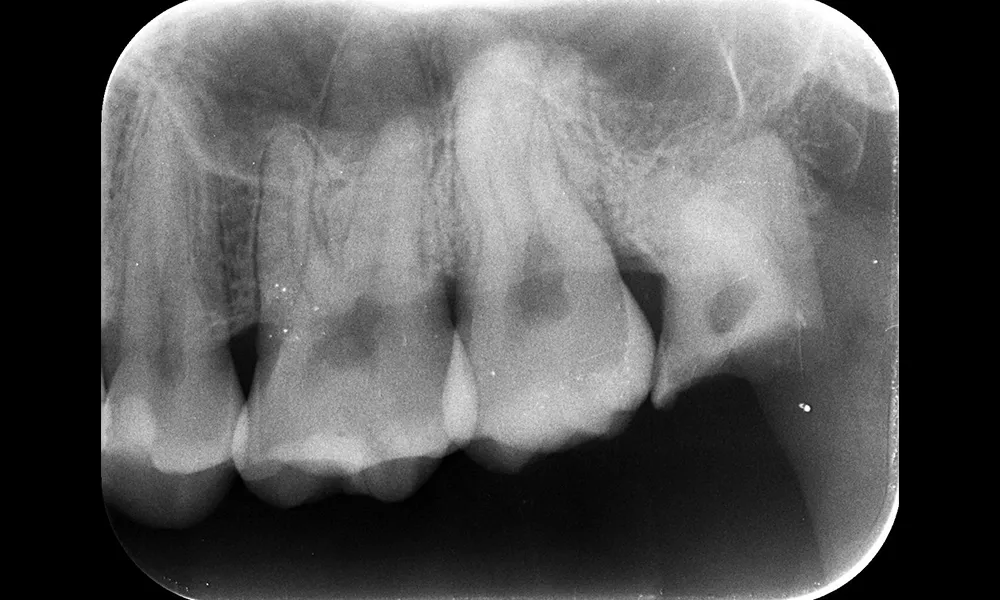

| 主訴 | 親知らずととなりの歯の間に食べかすが詰まって痛い |

| 治療期間 | 30分 |

| 治療費 | 1歯 約5,000円 |

| 治療内容 | 下の親知らずの抜歯を行い縫合し、翌日以降に消毒、抜糸を行った。 |

| 治療のリスク | 術後の疼痛、腫脹、痺れ |